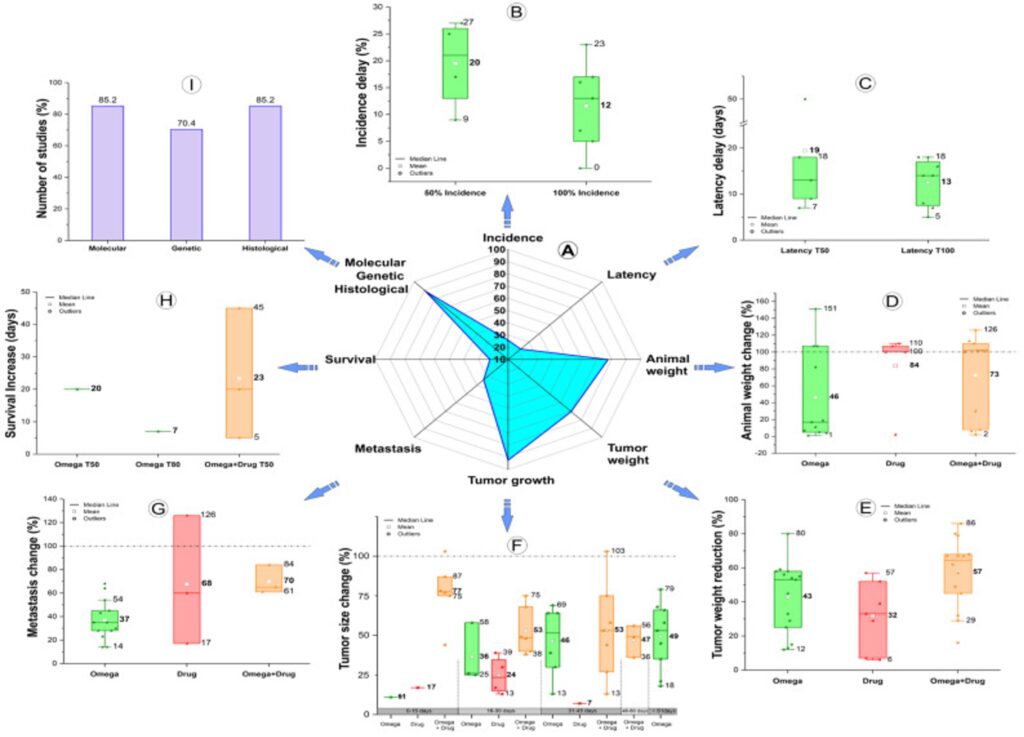

研究指出:Omega-3搭配治療,腫瘤轉移最高降低84%,存活時間平均延長23天

一篇來自《Nutrients》(2023)期刊的系統性回顧研究(研究連結),分析近5年共679篇文獻,最終納入27項動物實驗研究,探討Omega-3脂肪酸(EPA、DHA)在乳癌「預防」與「治療輔助」中的作用。研究設計涵蓋不同乳癌模型(細胞移植、基因轉殖、藥物誘導),並比較Omega-3單獨使用與「搭配化療藥物」的效果,觀察腫瘤大小、轉移、存活率與分子機制等指標。

研究結果顯示,Omega-3若搭配抗癌藥物效果最明顯,在早期(15天內)可顯著降低腫瘤體積與重量,腫瘤重量平均下降可達57%,轉移抑制效果甚至達61~84%;同時也觀察到整體存活時間增加約23天。若單獨補充Omega-3,則在長期使用下,對於延緩腫瘤發生(延後約20%)、降低轉移(最高達70%)與抑制腫瘤成長仍具有明顯效果,但強度不如與藥物併用。

整體結論指出,Omega-3脂肪酸並非單一抗癌解方,但作為「輔助療法」具有高度潛力,能透過抗發炎、抑制腫瘤增殖、促進癌細胞凋亡與影響基因表現等機制,提升傳統治療效果,同時改善患者預後。不過目前最佳劑量與人體實際應用仍需更多臨床研究確認。